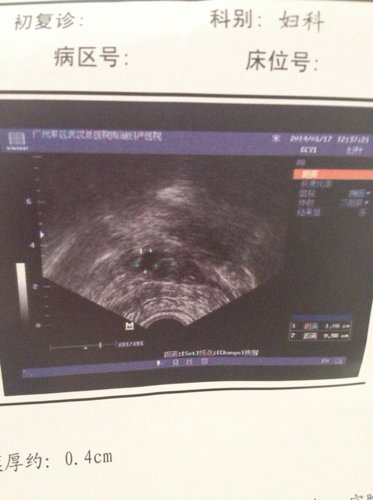

近期月经12月21号来,28完全干净今天1月17号做的这个B超,想咨询,卵巢还可以吗?卵泡多不

病情分析: 你好:;看你的超生检查结果,显示现在带有节育环,内膜薄,卵巢内有多个卵泡发育,没有发育成熟的,所以可能会影响怀孕的。 指导意见: 如果想要怀孕需要先取出节育环,然后观察三四个月还内膜是否正常,卵巢内的卵泡看是否多个,这是对于怀孕很重要的,注意做激素六项检测看是否多囊卵巢综合征。